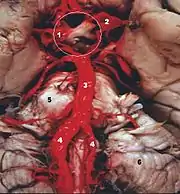

Sistema vertebro-basilar

El sistema vertebro-basilar (VBS en inglés) es el grupo de arterias intracraneales que irrigan el tronco encefálico, el cerebelo y el cerebro posterior. Este sistema es el único en la anatomía humana, en que dos arterias diferentes se fusionan y se continúan en una arteria única. La reducción o detención del flujo sanguíneo en este sistema, determina síntomas pasajeros o lesiones neurológicas permanentes.

Anatomía

Las dos arterias vertebrales y la arteria basilar proporcionan sangre a la parte posterior del círculo arterial cerebral y se anastomosa con la parte anterior del círculo, irrigado por las arterias carótidas.